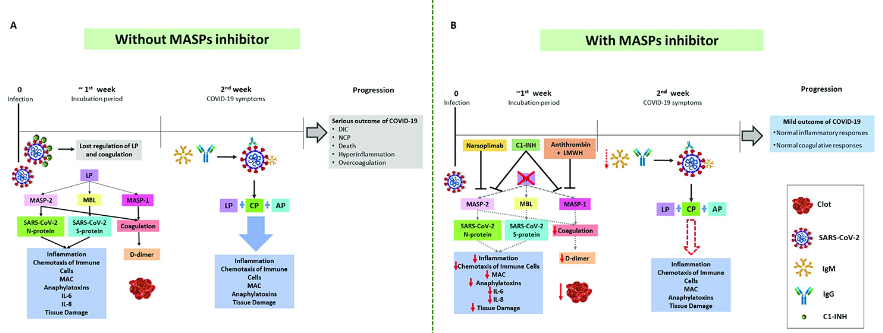

補體與凝血級聯信號通路(complement and coagulation cascade signaling pathway)與疾病的關系

補體和凝血級聯信號通路在維持機體免疫健康方面起著至關重要的作用。下面將對這兩種信號通路進行詳細介紹。一、補體(Complement)1